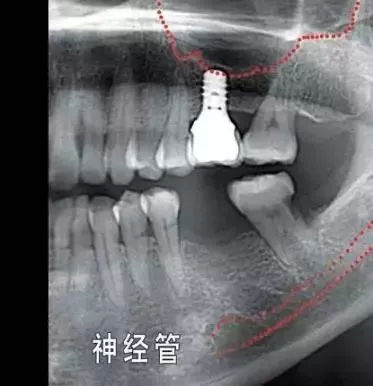

就种植手术本身而言,患者颌面部一些重要结构(例如下颌神经,上颌窦) 的位置和形态会增加手术风险和操作难度,为避免因手术损伤这些重要结构,医院会要求患者手术前拍摄3D X光片作为参考,以便牙医结合这些材料具体分析手术的风险程度。